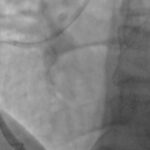

Jego specyfika polega na tym, iż lekarze użyli minimalnej ilości kontrastu w trakcie angioplastyki wieńcowej, czyli naprawy zwężeń w tętnicach wieńcowych u pacjenta cierpiącego na chorobę wieńcową.

Michał Tarnowski, kierownik oddziału kardiologii w Szpitalu Specjalistycznym w Sandomierz zwrócił uwagę na to, iż pacjent, u którego przeprowadzono ten zabieg, miał także liczne obciążenia w postaci zaostrzenia choroby nerek i niewydolności serca, dlatego był wcześniej odpowiednio przygotowany do tej procedury.

W skład zespołu lekarskiego, który wykonał zabieg wszedł również dr nauk medycznych Piotr Wańczura ze szpitala MSWiA w Rzeszowie.